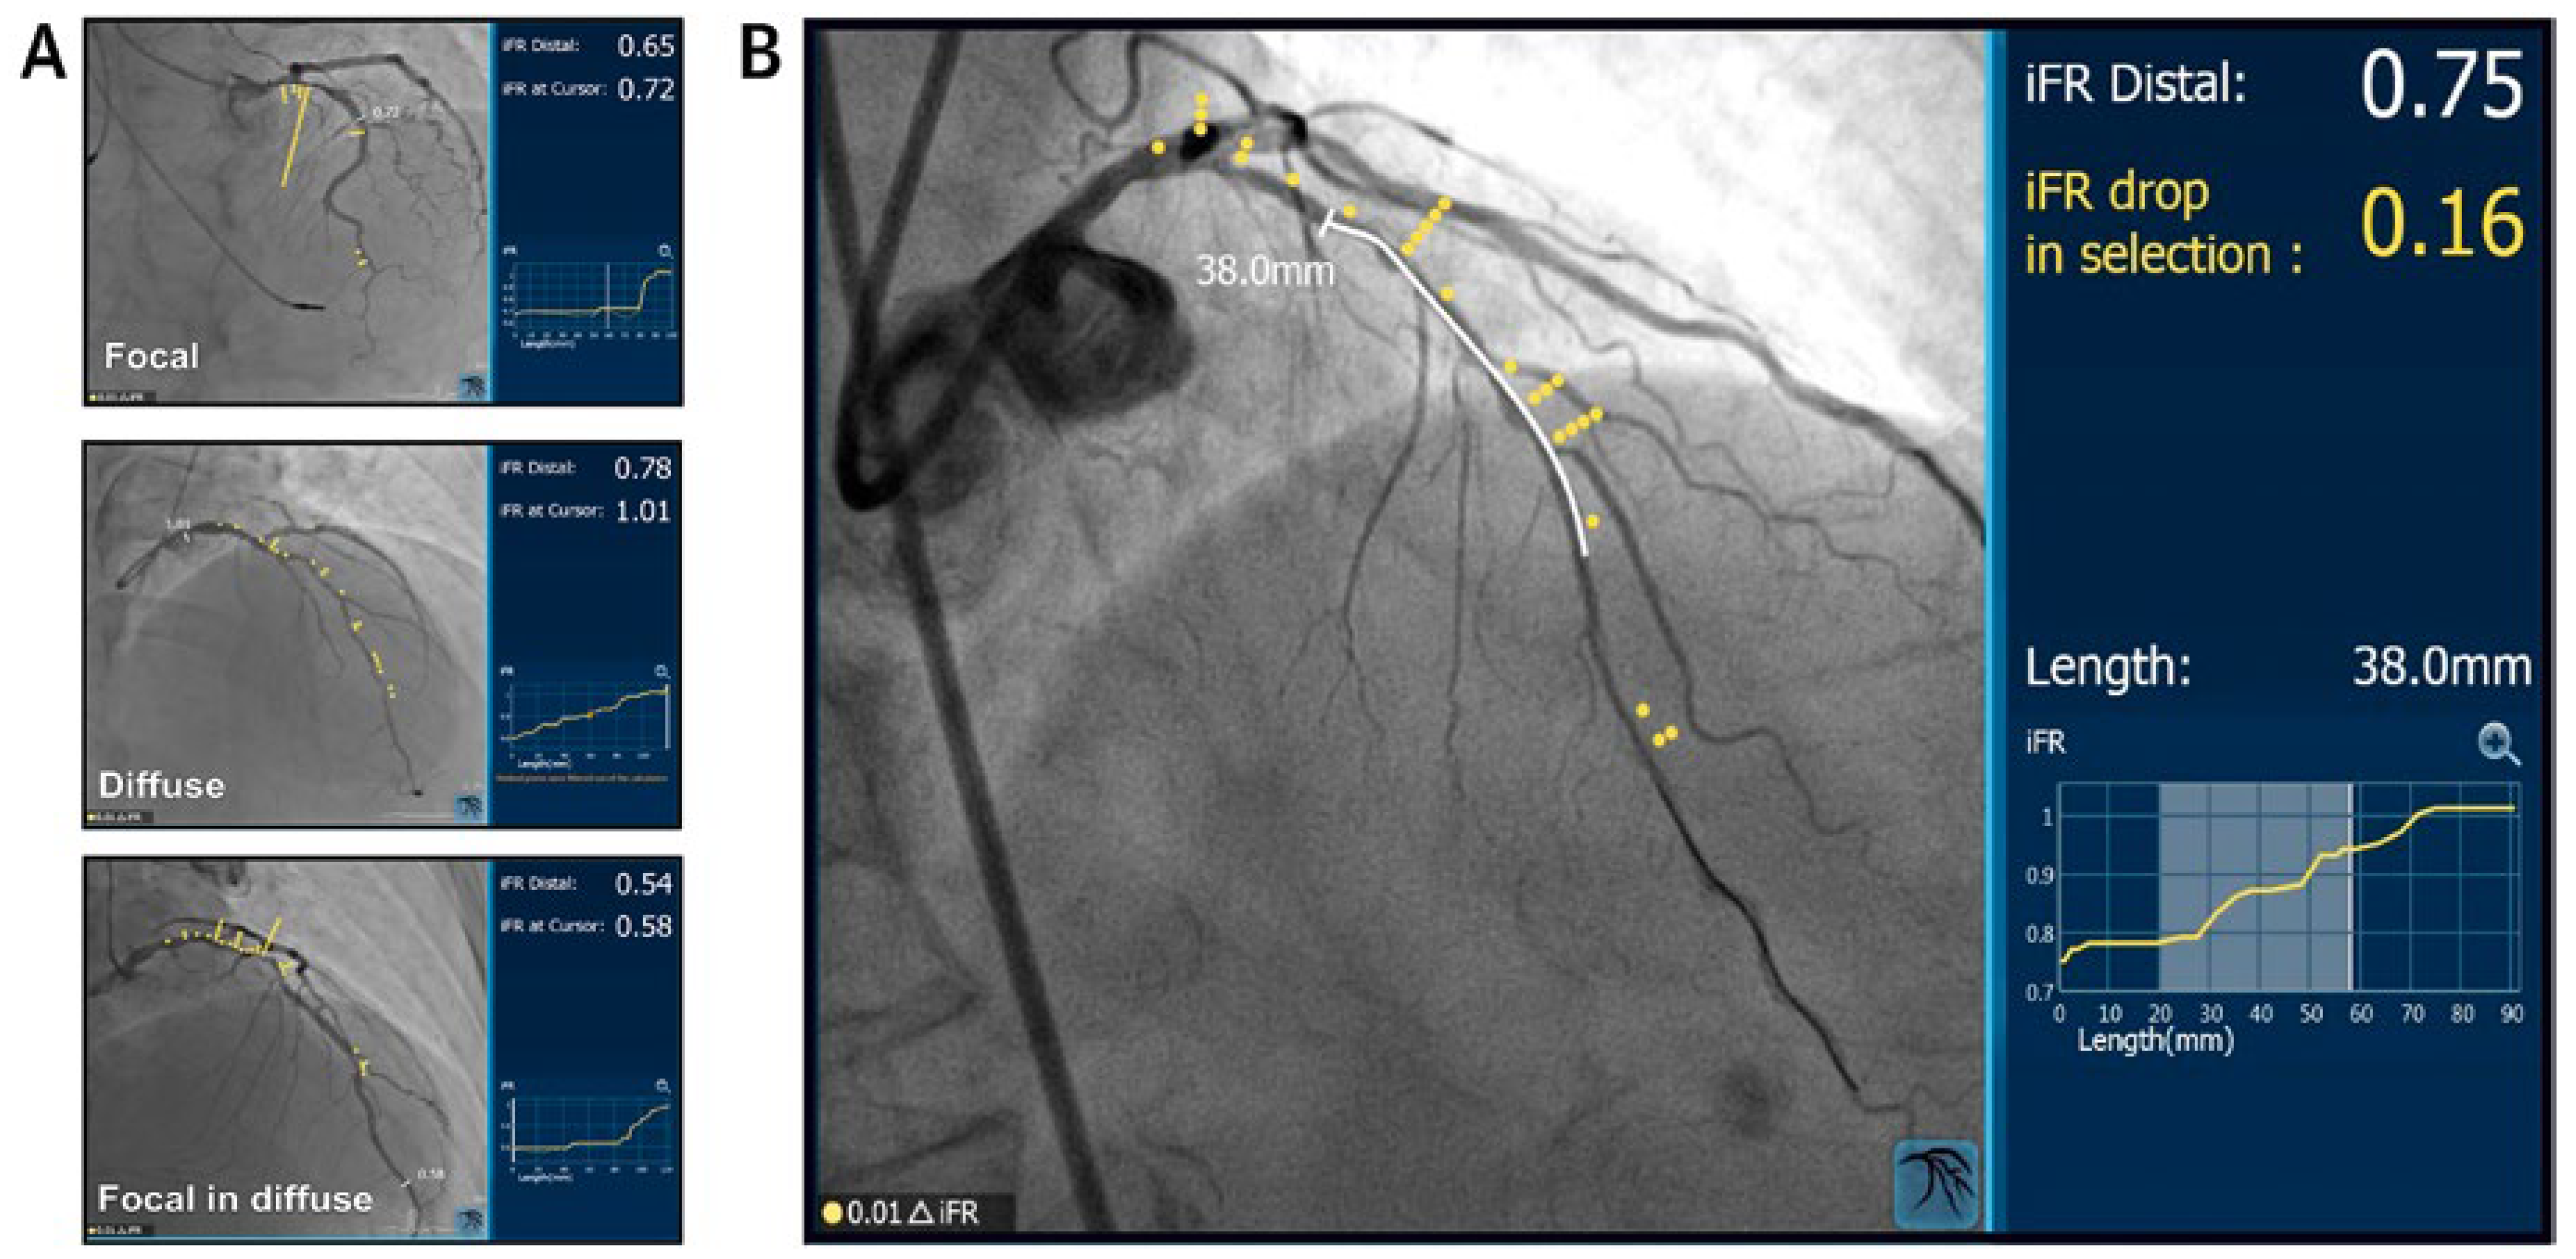

Figure 2.

iFR pullback. (A) iFR pullback recording throughout the coronary vessel. Post hoc co-registration of the iFR pullback trace with the coronary angiogram identifies pressure loss along the length of the vessel and distinguishes focal from diffuse disease. (B) Prediction of the post-PCI iFR result. Virtual PCI calculates the expected post-PCI iFR result for the area selected for PCI. LAD: left anterior descending artery; PCI: percutaneous coronary intervention. Reprinted with premission from Elsevier from Nijjer SS, Sen S, Petraco R, Escaned J, Echavarria-Pinto M, Broyd C, et al. Pre-angioplasty instantaneous wave-free ratio pullback provides virtual intervention and predicts hemodynamic outcome for serial lesions and diffuse coronary artery disease. JACC Cardiovasc Interv. 2014;7(12):1386–96.

Further developments of the iFR algorithm combined with real-time computer to track the pressure-wire movement progressively removed the remaining technical barriers to facilitate complete integration of the iFR pullback concept into clinical practice. The iFR co-registration technology uses a dedicated proprietary software to create a fully integrated real-time physiological map of the coronary vessel under manual pullback that is co-registered with the patient coronary angiogram (Figure 3). The iFR co-registration technology permits the instantaneous calculation of predicted post-PCI iFR values, thereby determining the potential physiological benefit of different treatment strategies. Revascularisation strategies that maximise the physiological benefit with a minimum of stents over more extensive PCI approaches may be planned to potentially improve patient outcomes. Contrariwise, the iFR co-registration may identify patients for whom greater numbers or longer stents are required in order to achieve haemodynamic improvement. Finally, the iFR co-registration technology enables accurate physiological documentation of angiographically diffuse CAD, thus contributing to the tailoring of treatment strategies at a patient level and the choice appropriate alternative approaches to PCI (medical therapy or surgical revascularisation) in selected patients.

Figure 3.

iFR co-registration. (A) Co-registration of iFR pullback traces with corresponding coronary angiograms demonstrates three distinct patterns of pressure loss along the length of coronary vessels: focal stenosis, diffuse coronary disease, focal stenosis and diffuse coronary disease. (B) iFR co-registration allows virtual percutaneous coronary interventional (PCI) planning with real-time calculation of expected post-PCI iFR results. Reprinted with premission from Elsevier from Götberg M, Cook CM, Sen S, Nijjer S, Escaned J, Davies JE. The evolving future of instantaneous wave-free ratio and fractional flow reserve. J Am Coll Cardiol. 2017;70(11):1379–402.